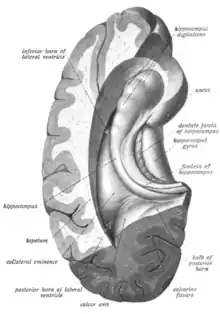

The hippocampus is a five centimetre long ridge of gray matter tissue within the parahippocampal gyrus that can only be seen when the gyrus is opened up.[15][16] The hippocampus is an inward fold of three-layered archicortex (one of three regions of the allocortex) into the medial temporal lobe of the brain, where it elevates into the floor of each lateral ventricle inferior horn.[17][18][19][20] The hippocampus stretches along its anterior-posterior axis, from the amygdala to the splenium of the corpus callosum, with the head, body, and tail regions as subdivisions of this axis.[21][15] The dentate gyrus, CA subfields, fimbria, and subiculum are divisions across the short axis, the proximal-distal axis.[21]

The hippocampus, and dentate gyrus that is folded into the hippocampal archicortex have the shape of a curved, rolled-up tube. The curve of the hippocampus (known as cornu Ammonis) uses the initial letters CA to name the hippocampal subfields CA1-CA4. CA4 is in fact the polymorphic layer or hilus of the dentate gyrus, but CA4 is still sometimes in use to describe the part of CA3 that inserts between the dentate gyrus regions or blades.[17][22]

It can be distinguished as an area where the cortex narrows into a single layer of densely packed pyramidal neurons, which curl into a tight U shape. One edge of the "U," – (CA4) the hilus of the dentate gyrus, is embedded into the backward-facing, flexed dentate gyrus. In humans the hippocampus is described as having an anterior and posterior part; in other primates they are termed rostral and caudal, and in rodent literature they are the ventral and dorsal part.[23] Both parts are of similar composition but belong to different neural circuits.[24] The dentate gyrus combined with other hippocampal regions form a banana-like structure, with the two hippocampi joined at the stems by the commissure of fornix (also called the hippocampal commissure).[19][25] In primates, the part of the hippocampus at the bottom, near the base of the temporal lobe, is much broader than the part at the top. This means that in cross-section the hippocampus can show a number of different shapes, depending on the angle and location of the cut.[26]